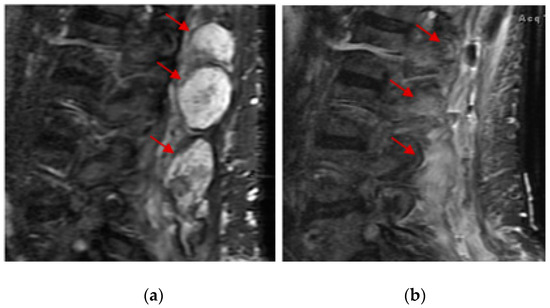

- Mori, Y.; Kinoshita, S.; Kanamori, T.; Kataoka, H.; Joh, T.; Iida, S.; Takemoto, M.; Kondo, M.; Kuroda, J.; Komatsu, H. The Successful Treatment of Metastatic Extraosseous Ewing Sarcoma with Pazopanib. Intern. Med. 2018, 57, 2753–2757. [Google Scholar] [CrossRef]